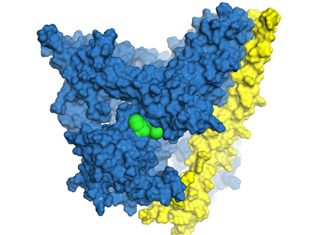

Pilin protein may combat the hairy problem of human pathogens

MWC investigations into the puzzle of a nanoscopic skyscraper – ‘the pilus’ – have sparked separate lines of research into novel vaccine delivery platforms which can target differe

Using 'molecular superglue' to build protein trees

Biological batteries, new vaccines and more cost-effective pharmaceuticals are just some of the potential benefits of Maurice Wilkins Centre research into the use of so-called mole

Chemistry, bio and immunology combine to target immune receptor

A Maurice Wilkins Centre collaboration across several scientific disciplines has led to a patent for a new immunotherapy drug.